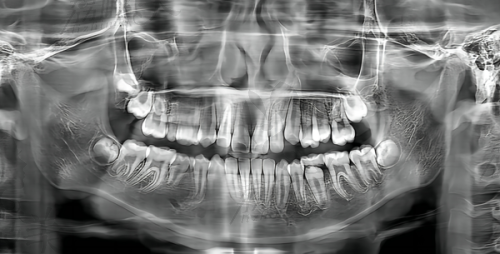

德国数字化根管治疗可不只是价格美丽,它的技术优势更是让人眼前一亮。传统的根管治疗就像是在黑暗中摸索,医生只能凭借经验和手感来操作,难免会出现一些误差。而德国数字化根管治疗就像是给医生配备了一个超级“导航系统”。它利用精良的数字化设备,能够精细地定位牙齿内部的根管系统,就像给牙齿做了一个 3D 地图,让医生对牙齿的情况了如指掌。这样一来,治疗过程更加精细、效率高,大大减少了治疗时间和患者的痛苦。而且,数字化技术还能实时监控治疗过程,确保每一个步骤都做到尽善尽美,治疗成效自然更有保护。比如说,在清理根管时,能够更完全地清除感染物质,降低了复发的风险;在填充根管时,也能确保填充的密实度,让牙齿修复得更加坚固。有了德国数字化根管治疗,就相当于给牙齿请了一位专精的“私人医生”。